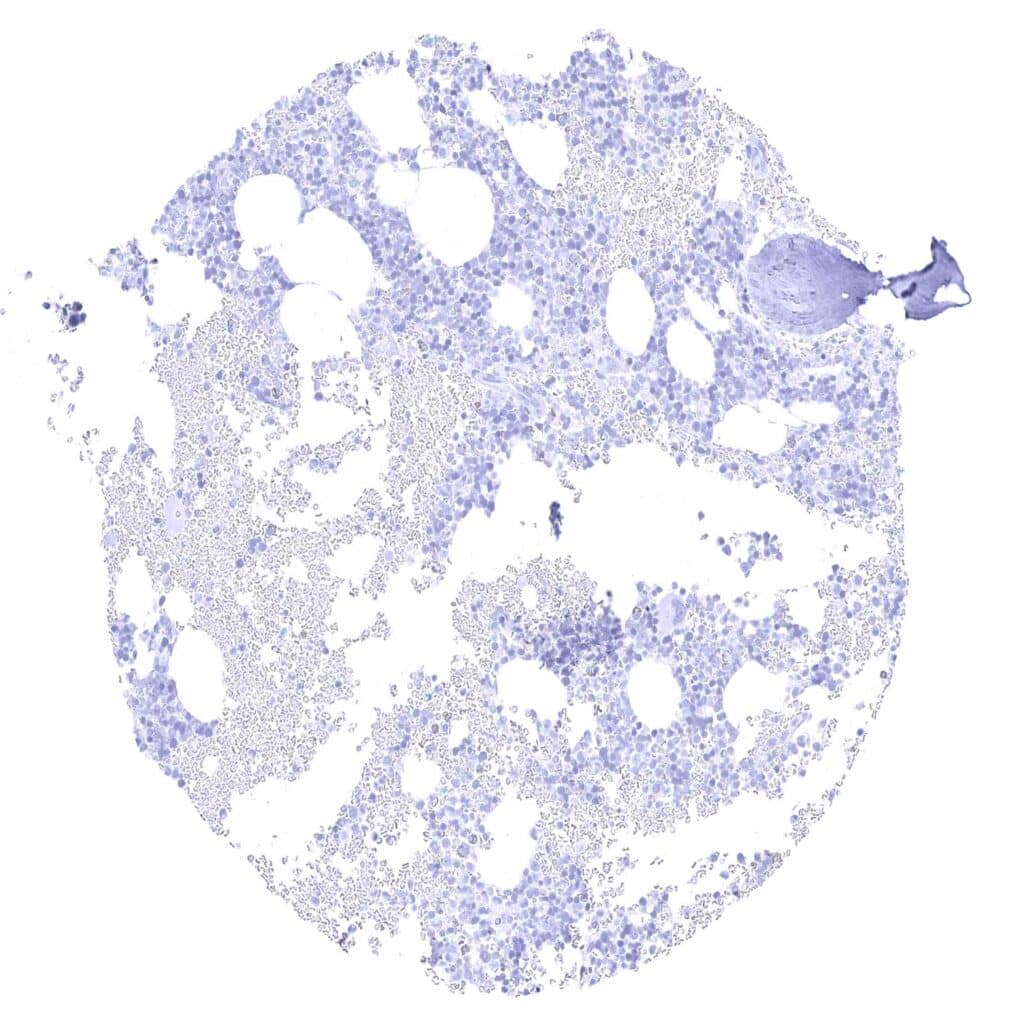

Lymph node – Membranous CD70 staining of variable intensity in subsets of cells (mostly lymphocytes). Most CD70 positive cells are interfollicular.